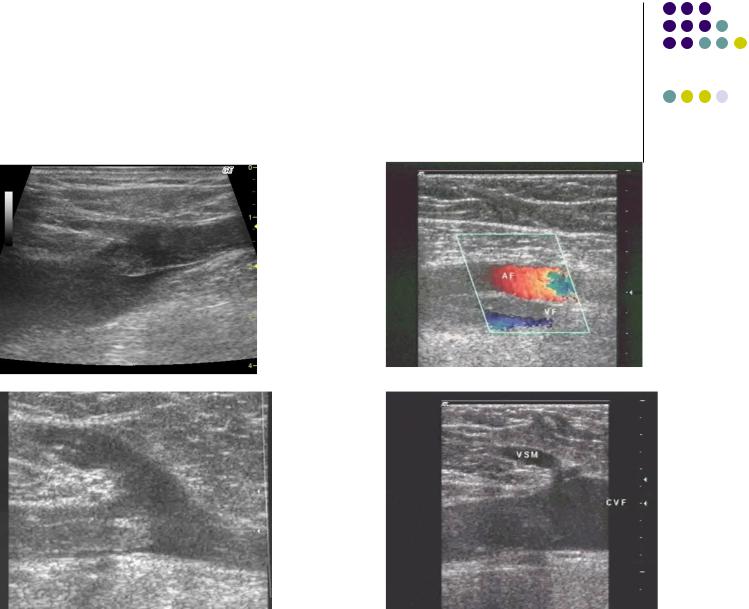

Ультразвуковое ангиосканирование

при ТГВ